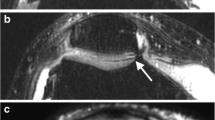

Three-tesla imaging allowed increased SNR, faster imaging, and increased resolution. A chemical shift artifact was more noticeable at 3 T with both the 31.25- and the 62.5-kHz bandwidths although it was less with the higher bandwidth (Figs. 1, 2,3).

Chemical shift artifact. A Sagittal proton density image (31.25kHz, 3,000/15 eff, echo train 8) shows a chemical shift artifact adjacent to the subchondral bone plate (long arrows) and the vessels in the femoral condyle (short arrows). B Sagittal proton density image at higher bandwidth (62.5 kHz, 3000/12 eff, echo train 8) still shows the chemical shift artifact but it is less prominent than in A

Chemical shift artifact. A Sagittal proton density image (62.5 kHz, 3,000/12 eff, echo train 8) shows a chemical shift artifact adjacent to the subchondral bone plate (long arrow) and the vessels in the femoral condyle (short arrows). B Sagittal proton density image (62.5 kHz, 3,000/12 eff, echo train 8) shows that when the frequency is changed 90° the chemical shift artifact disappears from the subchondral bone and the artifact adjacent to the vessels moves 90° clockwise (short arrows). The residual increased signal at the margins of the tibial cortex (long arrows) is more difficult to explain and may represent a chemical shift artifact in the slice-selection direction

Chemical shift artifact. A Sagittal proton density image (15.6 kHz, 4,000/24 eff, echo train 8) shows a chemical shift artifact with widening of the subchondral bone plate of the femur and thinning of the plate of the tibia (arrows). B With the frequency changed 90° the sagittal proton density image (15.6 kHz, 4,000/24 eff, echo train 8) shows the subchondral bone plate of the femur is now thinned posteriorly (long arrows). Note also the chemical shift artifact adjacent to the vessels in the posterior femoral fat has moved 90° (short arrows)

In clinical practice a chemical shift artifact is certainly more noticeable at 3 T when compared with 1.5 T (Figs. 1, 2, 3, 4). The doubling of the separation between the resonant frequencies between fat and water leads to improved fat saturation but also introduces a chemical shift artifact. The artifact is apparent in the image as a spatial shift of fat in the frequency-encoded direction. When first tested at 3 T, our 1.5-T protocol had an artifact because of the fat shift. After increasing the scan resolution to 512 from 256 the artifact became significant, moving four pixels. To compensate for the chemical shift artifact, we increased the bandwidth from 31.25 to 62.50 kHz. Even with the higher bandwidth, the artifact is still seen, although it is not as distracting. With both bandwidths, we did not see any cases in which a chemical shift artifact obscured relevant diagnostic information. A subchondral bone plate chemical shift artifact is certainly very prominent at 15.6 kHz (Fig. 3); however, no clinical cases were investigated using this bandwidth. At 62.5 kHz, although still present it is less noticeable and we did not have any cases in which it affected our overall interpretation. It was difficult to explain the anatomic basis of some of the chemical shift artifact (Fig. 2). Some of this artifact may be from a chemical shift not in the frequency direction, but in the slice direction [16].